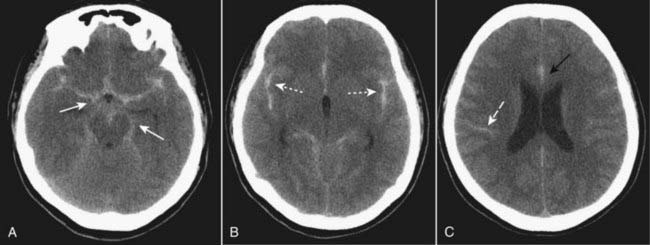

image Recognizing an acute subdural hematoma

On CT, acute subdural hematomas are crescent-shaped, extracerebral bands of high attenuation that may cross suture lines and enter the interhemispheric fissure. They do not cross the midline.

Typically, a SDH is concave inward towards the brain (epidural hematomas are convex inward) (Fig. 25-9A).

As time passes and they become subacute, or if the subdural blood is mixed with lower attenuating CSF, they may appear isointense (isodense) to the remainder of brain, in which case you should look for compressed or absent sulci or sulci displaced away from the inner table as signs of SDH (Fig. 25-9B).

Subdural collections may demonstrate a fluid-fluid level after 1 week, as the cells settle under serum.

image Chronic subdural hematoma

Chronic subdural hematomas are those present more than 3 weeks after injury.

Chronic subdural hematomas are usually low density compared to the remainder of the brain (Fig. 25-9C).

image

Figure 25-9 Acute, isodense, and chronic subdural hematomas.

A, There is a crescent-shaped band of high-density blood concave inward towards the brain (solid white arrow). Mass effect is present with herniation of the brain as indicated by the dilated contralateral temporal horn (dotted white arrow). B, As they become subacute, subdural hematomas become less dense and may be the same density (isodense) as the normal brain tissue (solid white arrow). You can recognize an isodense subdural by the unilateral absence or displacement of the sulci away from the inner table of the skull compared to the normal opposite side (solid black arrow). C, Chronic subdural hematomas (more than 3 weeks old) are usually of low density (solid white arrow) compared to the remainder if the brain. There is still mass effect demonstrated by displacement of the interhemispheric fissure (dotted white arrow) and compression of the lateral ventricle.